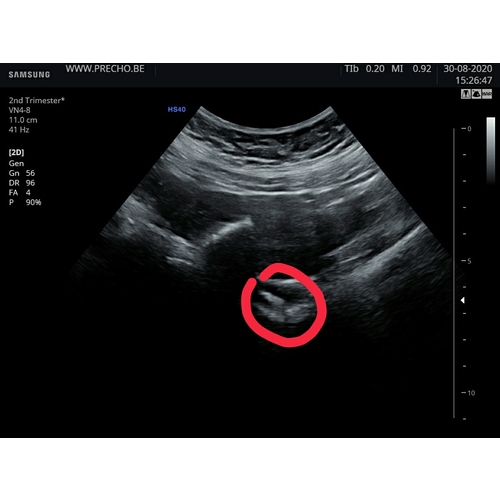

Hier echo 6+4 en ook in het hoekje geplakt wel kloppend hartje! Vrijdag weer echo en dan 8 weken

Ik heb maandag ook echo gehad bij 6+4. Was inwendig.

Was even zoeken. Het zat ook in een hoekje. Wel het hartje zien kloppen.

Wij ook precies hetzelfde verhaal. Met volle blaas en zowel inwendig als uitwendig nauwelijks wat te zien. Volgens mijn laatste menstruatie zat ik op 7+5. Maar eigen berekening ben ik nog niet zover. Later zag ze wat flikkeren en dat kon het hartje zijn. Nu gaan we donderdag as weer kijken, dan ben ik 8+3. Een week vol spanning. Hopelijk Dan wat meer te zien